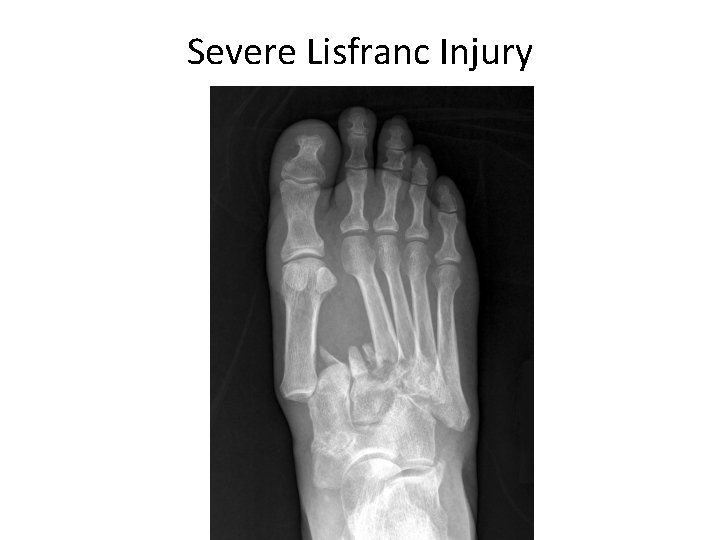

Severe Lisfranc Injury